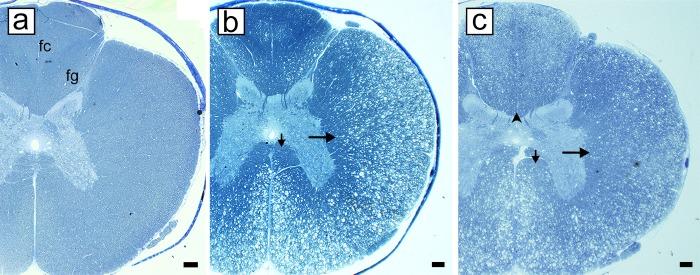

Irradiation of food at 50-55 kGy results in a profound, chronic demyelinating-remyelinating disease of the entire central nervous system (CNS) in cats, named Feline Irradiated Diet-Induced Demyelination (FIDID). This study examines the early stages of demyelination and long-term consequences of demyelination and remyelination on axon survival or loss. Myelin vacuolation is the primary defect leading to myelin breakdown, demyelination then prompt remyelination in the spinal cord and brain. There is no evidence of oligodendrocyte death. The spinal cord dorsal column is initially spared yet eventually becomes severely demyelinated with subsequent loss of axons in the core and then surface of the fasciculus gracilis. However remyelination of the sub-pial axons in the dorsal column results in their protection. While there was a lack of biochemical evidence of Vitamin B12 deficiency, the pathological similarities of FIDID with sub-acute combined degeneration (SCD) led us to explore treatment with Vitamin B12. Treatment led to recovery or improvement in some cats and neurologic relapse on cessation of B12 therapy. While the reason that irradiated food is myelinotoxic in the cat remains unresolved, nonetheless the neuropathological changes match exactly what is seen in SCD and its models and provide an ideal model to study the cellular and molecular basis of remyelination.